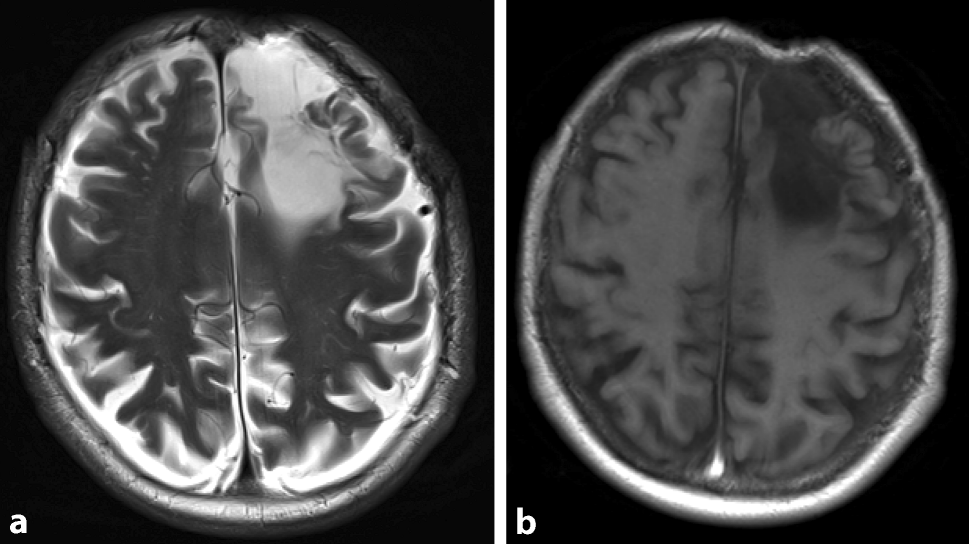

A 75-year-old man presented to the otorhinolaryngology outpatient clinic with a 3-month history of nasal airway obstruction. With anterior rhinoscopy, a livid-colored capillary expansion obstructing the whole nasal cavity was detected. A biopsy specimen was diagnosed as a capillary hemangioma, which was later resected endoscopically in sano. An additional finding of the initial physical examination was a frontal pulsating skin indentation with a central scar (Fig. 1; Video 1, Supplementary material). The patient reported a car accident that occurred 30 years ago as the origin of this indentation. No further information from the patient’s history or the medical record was available. Magnetic resonance imaging (MRI) of the face and brain was performed to assess the extent of the nasal hemangioma and, unrelated to the intranasal expansion, an arachnoid cyst below the osseous defect of the left frontal bone was detected with subsequent dilatation of the left lateral ventricle (Fig. 2). The patient’s medical history revealed no predisposing diseases or other relevant medical conditions. The diagnosis of a secondary posttraumatic arachnoid cyst was established [1]. On follow-up MRI, this arachnoid cyst without clinical symptoms was stable and remains under surveillance. This is a rare case of a pulsating frontal bone defect due to secondary posttraumatic arachnoid cyst with extension into the lateral ventricle.

Fig. 2

Secondary posttraumatic arachnoid cyst below the osseous defect of the left frontal bone with subsequent dilatation of the left lateral ventricle on cranial magnetic resonance imaging (a T2-weighted, b T1-weighted)